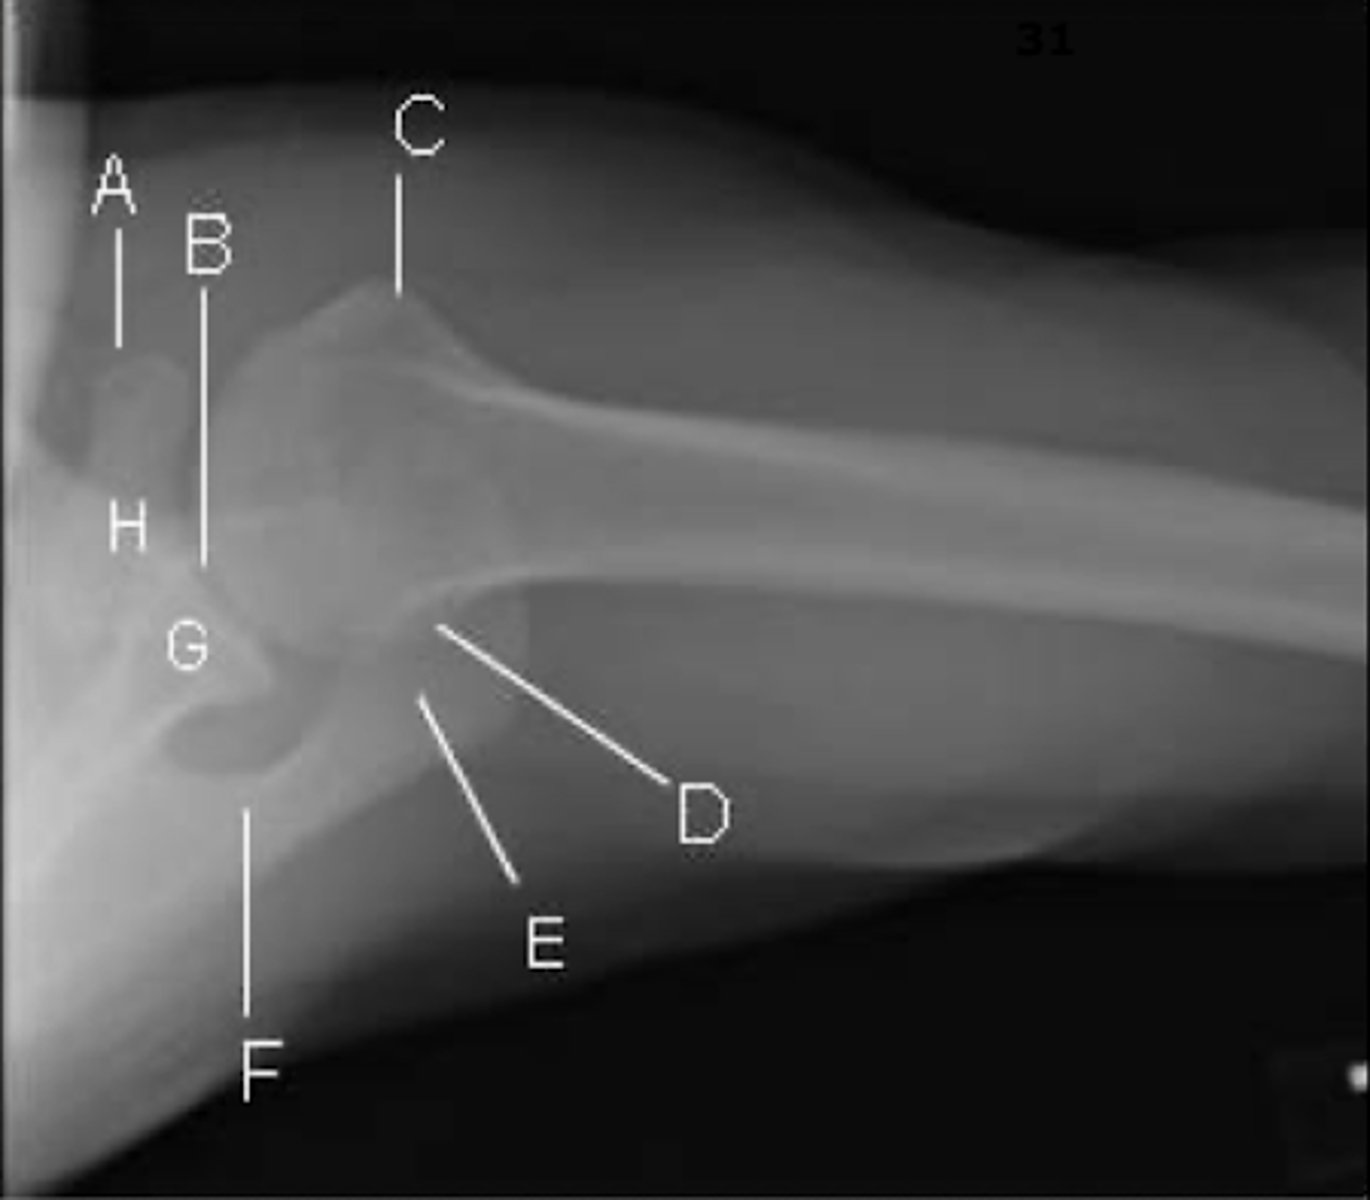

REVIEW: Shoulder XR (Axillary view)

A → coracoid process

B → glenohumeral joint

C → less tubercle

- externally rotated so will look more anterior

D → posterolateral humeral head

E → acromion

F → spine of the scapula

G → glenoid process

H → base of the coracoid